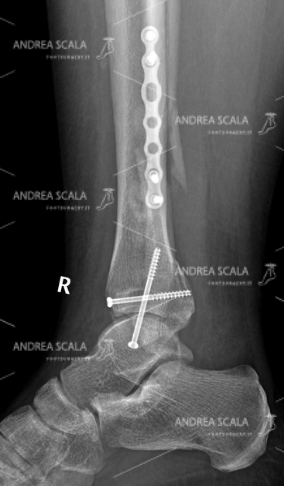

La RXgrafia anteriore della caviglia mostra la protesi della caviglia. 5 anni dopo la frattura, all’età di 39 anni, la paziente ha rifiutato l’artrodesi, cioè il blocco della caviglia e si è sottoposta all’intervento di protesi di caviglia. Si vede molto bene che la placca e le viti sul perone sono rimaste al loro posto indisturbate. Il perone non è stato toccato perché è un elemento anatomico che garantisce la stabilità della caviglia. Le componenti appaiono ben allineate all’asse della gamba.

La RXgrafia laterale della caviglia mostra la protesi della caviglia. Per quale motivo si sarebbe dovuto rompere nuovamente il perone? Perché avrebbe dovuto sacrificare una parte che era guarita? Perché avrebbe dovuto rompere di nuovo una parte che aveva impiegato tanto tempo a consolidare e a guarire? Per fare un favore a chi? Si nota che le componenti della protesi sono parallele al piano d’appoggio al suolo.